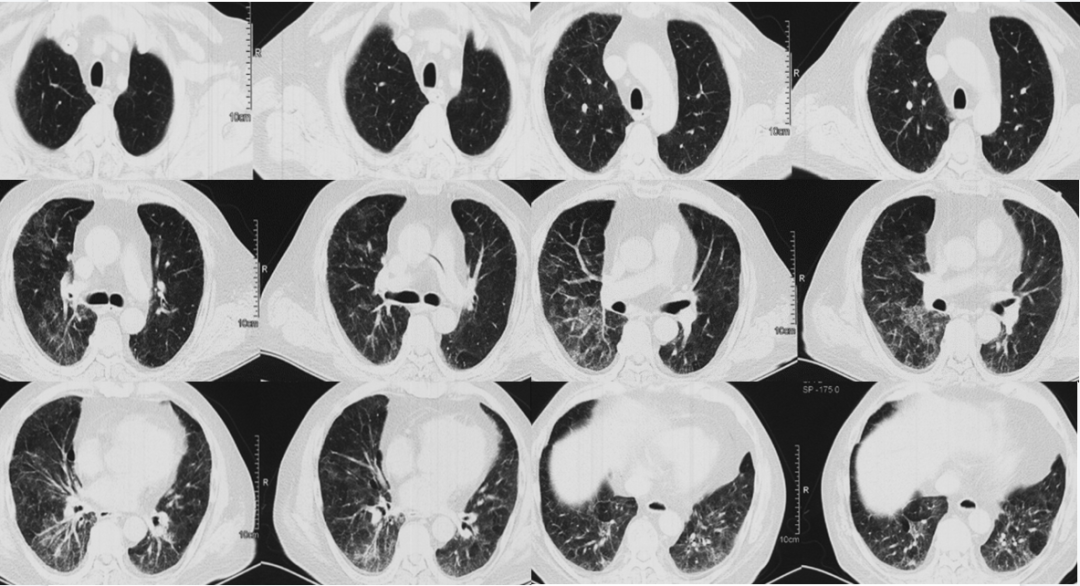

入院前1天(2021年1月23日)就诊于北京安贞医院发热门诊。血常规:WBC 12.1×109/L,NEU% 78.3%;动脉血气:(吸氧不详)pH 7.52,PaCO2 21.2 mmHg,PaO51.4 mmHg,SaO2 86.9%。胸部CT:双肺弥漫磨玻璃渗出伴小叶间隔增厚,病变进展(图2)。予赖氨匹林退热、多索茶碱平喘、美罗培南抗感染等治疗,患者呼吸困难、发热等症状未缓解。

图片

图2  患者胸部CT(2021-01-23,外院)